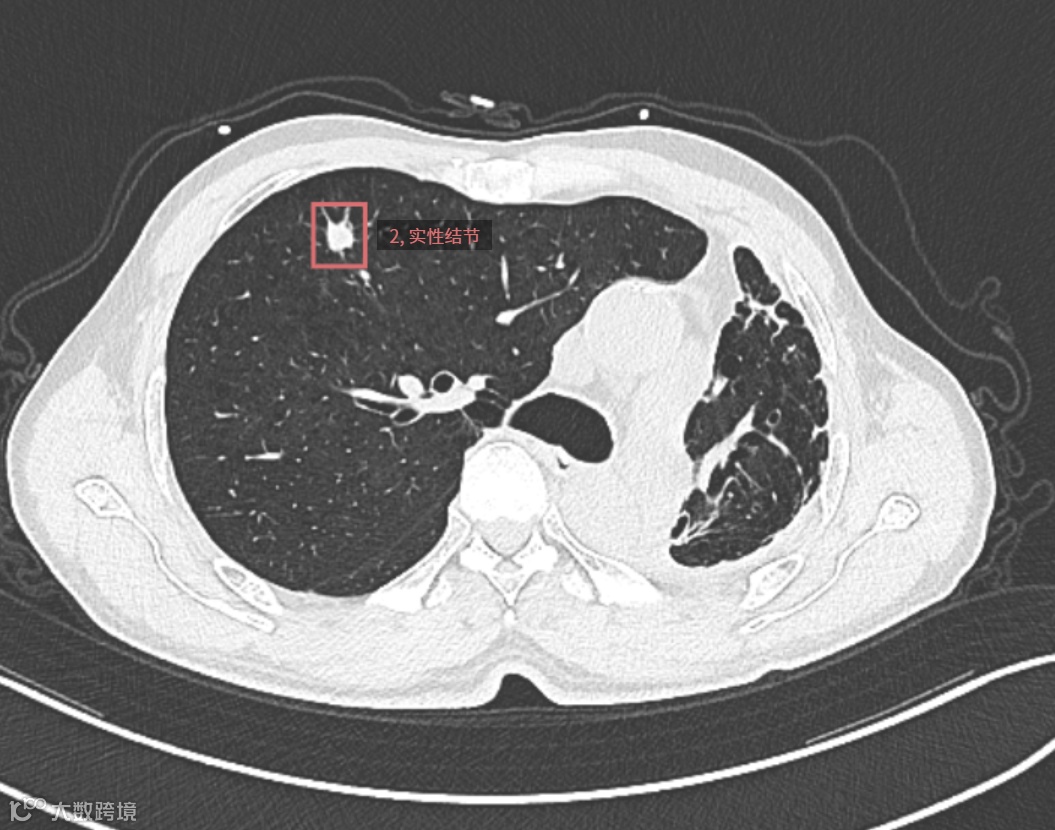

检查所见:患者接受左下肺切除术后,残余肺组织以左肺上叶尖段为主,伴右肺代偿性过度膨胀及形态结构改变。右肺上叶前段可见一实性结节,大小约13.6mm×11.5mm,边界尚清,密度欠均,边缘呈浅分叶状。余右肺散在少许条索影及肺气肿表现。

▲▲▲检测框所指为结节